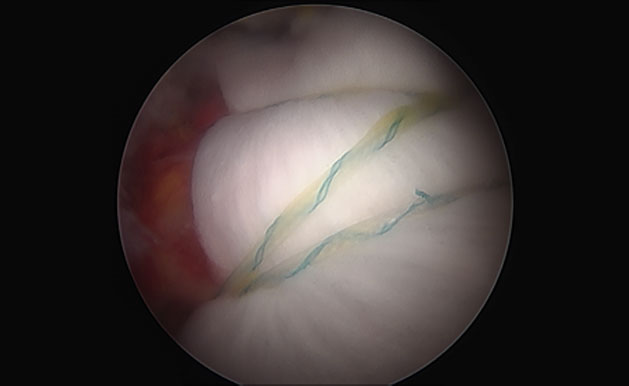

회전근개 패치 보강술은 파열된 힘줄을 잘라내지 않아 손상이 덜하며 무리하게 끊어진 힘줄을 당기지 않고 동종진피(acellular ermal matrix)를 이용해 끊어진 부위를 덮어 꿰매주는 시술로 재파열률을 현저히 줄인 선진수술법 입니다.

리제네텐 콜라겐 임플란트는 파열된 회전근개 부위에 콜라겐 패치를 덧대어 새로운 힘줄로 성장할 수 있게 지원하고 6개월 이내 점진적으로 흡수되어 새로운 힘줄과 같은 조직층으로 바뀝니다.